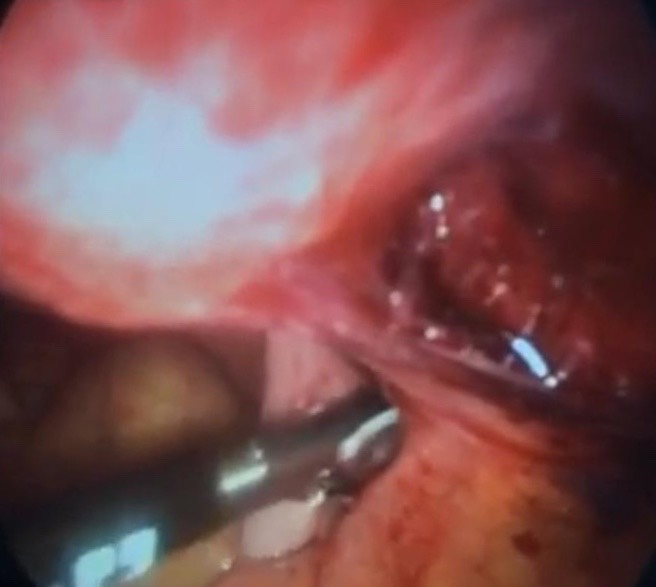

An adnexal mass (mass of the ovary, fallopian tube, or surrounding connective tissues) is a common gynecologic problem. In the United States, it is estimated that there is a 5 to 10% lifetime risk for women undergoing surgery for a suspected ovarian neoplasm. Adnexal masses may be found in females of all ages, from fetuses to older adults, and there are a wide variety of types of masses.  Today, the surgical treatment has become more conservative and less invasive; hence, a laparoscopic approach in the presence of benign cysts has become a golden standard. In the past, patients with previous abdominal surgery were discouraged from undergoing laparoscopic surgery because of its increased risk of bowel injury caused by needle and trocar insertion. Complications occur two times more frequently in patients with previous laparotomy in a study of long series. The potential risk for injury of organs adherent to the abdominal wall during veress needle or trocar insertion as well as the necessity for adhesiolysis and its attendant complications are the two major specific problems constraining surgeons from performing laparoscopic cystectomy/ oophorectomy for patients with previous abdominal surgery. Herein, we report a case of a 32-year-old woman P4 + 2 with history of previous four cesarean section and a following laparotomy for interval sterilization presented to our clinic with abdominal mass, discovered by ultrasound scan, managed by a laparoscopic approach.